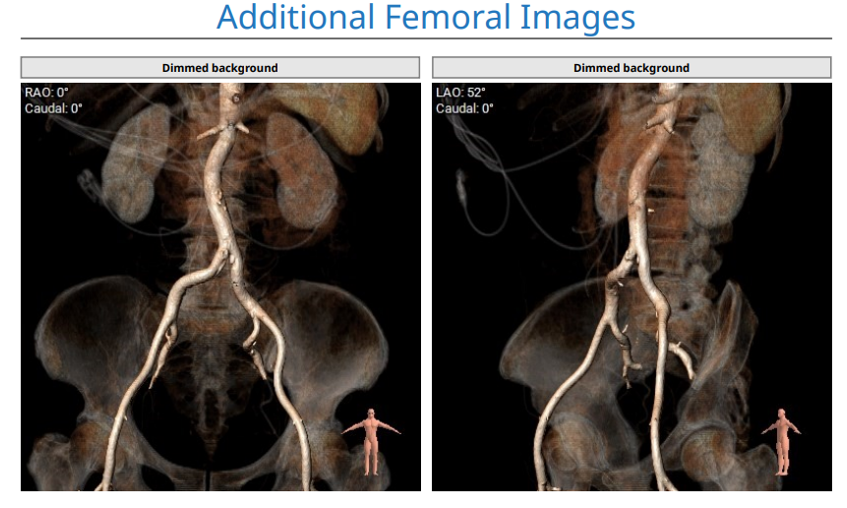

股动脉入路: